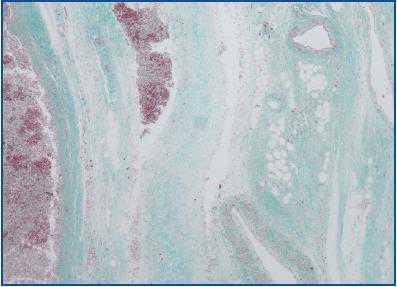

The diagnostic criteria were based on the histology: the biopsied tissue had to present fibrosis with inflammatory infiltrate containing lymphoplasmacytic cells and macrophages; it should be predominantly perivascular and contain irregular bands of collagen (figure 1). In the case of a radiological diagnosis, a fibrotic band around the aorta or iliac vessels would confirm IRF. In both cases, patients with infectious diseases (especially tuberculosis in this context), neoplasia(especially lymphoproliferative syndromes), sarcoidosis and autoimmune diseases were ruled out in accordance with the clinical and analytical criteria.

Figure 1.